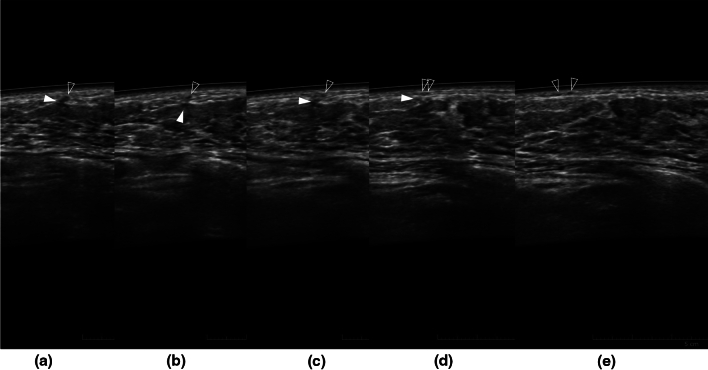

Fig. 4.

Left breast ABUS images of a 36-year-old woman at 24 weeks 6 days of pregnancy. Images are arranged from left to right in the order a–e. The ductal structure ran longitudinally across the premammary fascia (a) and then penetrated the superficial fascia (b, c) and ran laterally just below the dermis (d, e), and therefore, they were vascular structures. The filled arrowhead indicates the deeper structure, and the open arrowhead indicates the shallower structure. However, the deeper vessel is obscure in e